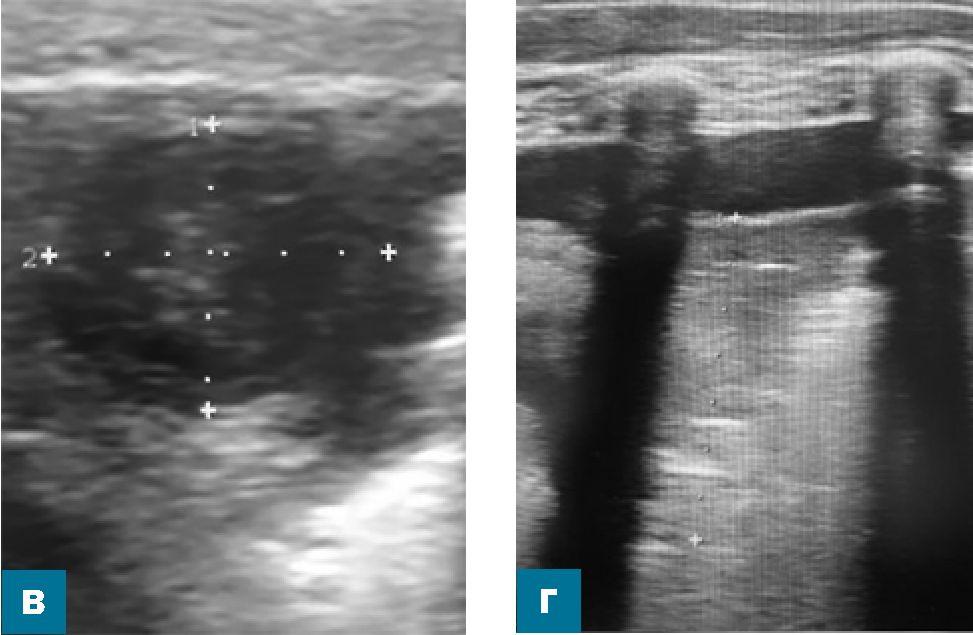

Результаты ультразвукового исследования по существу подтвердились после получения данных компьютерной томографии органов грудной клетки с контрастным усилением, проведенной на следующий день (рис. 3).

Рис. 3. Компьютерные томограммы органов грудной клетки мальчика Б. на пятый день болезни (нативное исследование и с контрастным усилением) в аксиальных плоскостях

Протокол

На полученных томограммах толщиной среза 1 мм и мультипланарных реконструкциях до и после контрастирования «Омнипак 300»:

- Слева: на уровне нижних отделов косой щели (на границе 5 и 8 сегментов, прилегая к диафрагме) определяется округлой формы образование, диаметром 15 мм в аксиальной плоскости, с четким неровным контуром, КТ-плотностью +54 HU, в центре участок гиподенсивной плотности, +19 HU, размером до 7 х 7 мм. Определяется утолщение междолькового интерстиция в 5 сегменте и нижней доле легкого, субплевральное неравномерное уплотнение легочной ткани в 9 и 10 сегментах.

Жидкость в левой плевральной полости по задней поверхности нижней доли до 7 мм.

- После контрастирования определяется накопление контрастного вещества в капсуле образования до +110 HU, в центральных отделах контраст не накапливается.

Заключение: КТ-картина может соответствовать абсцессу левого легкого, перисциссуриту слева. По-лисегментарная пневмония слева, жидкость в левой плевральной полости.